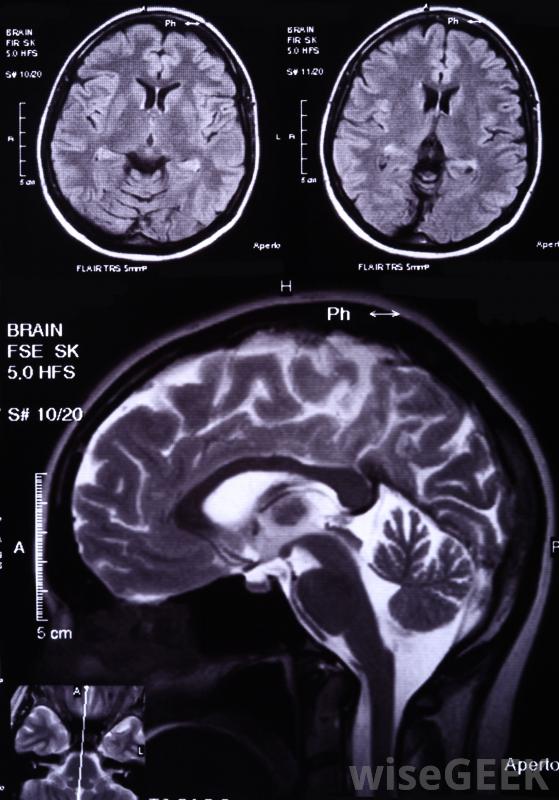

脑白质疏松症患者患脑血管疾病和痴呆症的风险增加,这种疾病不一定存在于患者身上,通常通过计算机断层扫描(CT)或磁共振成像(MRI)来检测到这种疾病。如果他们真的出现了,常见的症状包括身体各个部位的运动功能障碍、步态不均和认知障碍

脑白质疏松症通常会在脑部核磁共振扫描中发现医生可能会向白质疏松症患者推荐其他几种检查方法。其中一些用于跟踪疾病的进展,而另一些则用于确定病情是否导致了其他问题,如该地区的血管阻塞。医生通常会定期检查胆固醇水平和血液病人的压力。其他检查可能包括颈动脉超声,压力测试,经颅多普勒检查,或者心电图检查(EKG)。